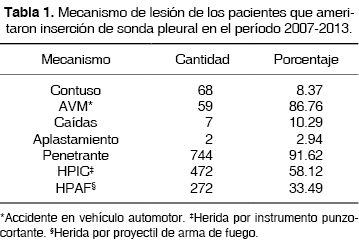

Se incluyeron 812 pacientes 758 (94.27%) hombres y 54 (6.65%) mujeres de 18 a 45 años de edad, con media de 29.81 años, 68 (8.37%) tenían antecedente de traumatismo torácico contuso y 744 (91.62%) de traumatismo penetrante, 472 (58.12%) por herida por instrumento punzocortante y 272 (33.49%) por herida por proyectil de arma de fuego. 459 (56.52%) tenía otras lesiones asociadas: 298 en extremidades (36.69%), 106 en abdomen (23.09%) y 55 en cráneo (11.98%) (tabla 1).